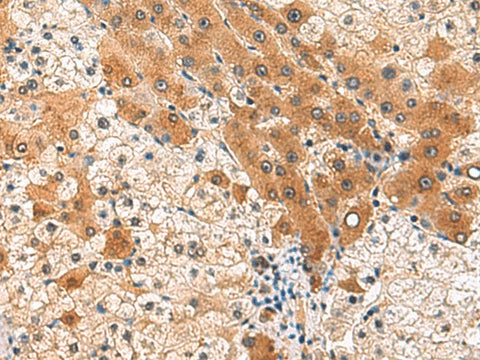

PCYT2 Polyclonal Antibody Reactivity Human

Reactivity Human, Mouse, Rat

Applications IHC

IHC 1:80-1:400